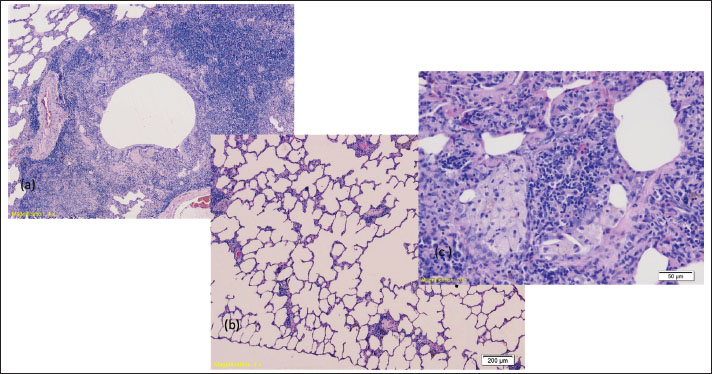

The lungs of all examined rats showed signs of acute bronchitis and bronchiolitis along with initial bronchopneumonia (Fig. 3 a). Focal acute emphysema (Fig. 3 b) and focal clusters of foamy macrophages (Fig. 3 c) were also observed.

Fig. 3. (a) Signs of bronchiolitis and consolidation of the lung parenchyma with congestion of blood vessels (HE, 4×); (b) hyperthermia-41 group: Initial signs of emphysema of the lung parenchyma (HE, 4×); heat stroke-44 group: consolidated lung parenchyma, with infiltration of inflammatory cells and the presence of small groups of foamy macrophages, the remains of aerated alveoli are observed (HE, 20×).

Significant pathological changes were observed in the lung tissue samples. Notable pathological alterations, including inflammation, necrosis, degeneration, hyperplasia, and fibrosis, were documented, and representative characteristics were selected for the overall assessment. Lung injury assessments were based on alveolar wall thickening, congestion, and inflammation. The lungs appeared heavy, with cut sections revealing severe pulmonary edema and congestion, as well as subpleural hemorrhages. All hyperthermic rats exhibited pronounced lung congestion and hemorrhage, with tissue samples indicating acute bronchitis, along with symptoms of initial pneumonia. We also noted instances of focal acute emphysema and foamy macrophage accumulation. Apart from the liver, brain, and kidneys, the lungs are the organ most significantly affected during heatstroke, i.e., hyperthermia (Marchand and Gin, 2022). Pulmonary edema with pulmonary congestion is a common complication that develops in patients after a heat stroke, especially if they were not adequately hydrated. The reasons for the occurrence of the resulting pulmonary edema are multiple and include excessive and inadequate fluid replacement, endothelial injury, acute kidney injury, and transient heart muscle dysfunction. A high incidence of acute respiratory distress syndrome with as much as 75% mortality is observed in patients with heatstroke (Wallace et al., 2007). In fact, lung involvement is part of a systemic response. Pathological changes in the lungs of rats occurred upon exposure to a temperature of 39°C in the form of blood vessel dilation, congestion, and lung matrix thickening. The congestion became more pronounced with the increase in temperature, with the presence of bleeding in the alveolar space, desquamation of epithelial cells, and damage to the structure of the pulmonary alveoli (Wallace et al., 2007).